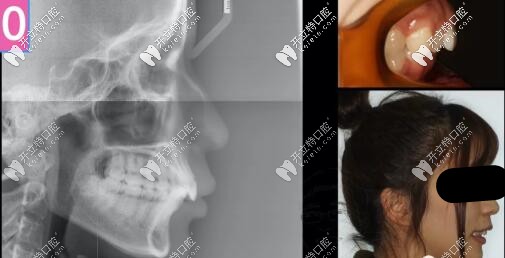

26歲女孩,來診主訴:嘴凸,大笑露牙齦,強烈訴求是解決嘴凸問題。

側貌微凸,深覆合

右側磨牙尖牙關系II類,左側I類,

深覆合覆蓋5mm,下頜牙弓擁擠度5mm

側位片提示:

骨性II類,均角,上前牙舌傾,下前牙唇傾前凸

齙牙是否拔牙

那么矯正拔牙還是不拔牙?4項指標提示不拔牙,真心不敢拔!

計劃支抗釘整體推上頜牙列向后、壓低上牙來解決深覆合和微凸問題,選用了標準轉矩DamonQ托槽。

正畸拔牙

此時再來看看是否能拔牙

兩項指標變了,可以拔牙,

治療計劃更新:拔上4下5,左側維持關系,拔上4下4

骨性二類齙牙單純正畸側貌效果圖

骨性二類凸嘴單純正畸牙齒內收3-4mm側貌效果圖

上前牙大量的壓低和內收,深復合改善。